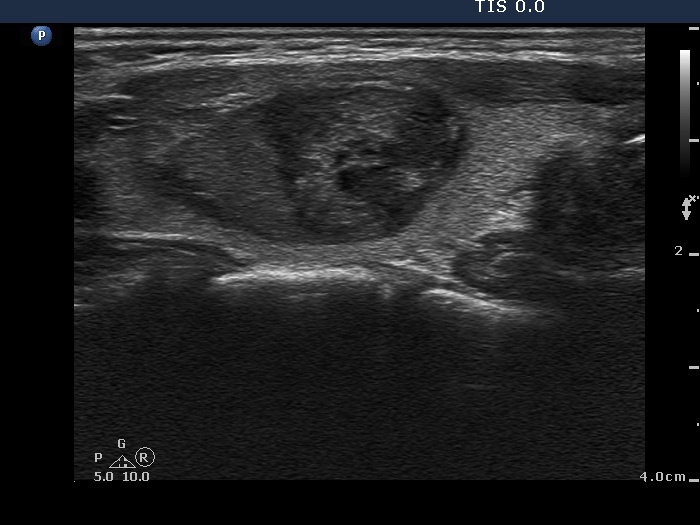

Ethanol sclerotherapy: other examples - Case 3: treatment of a gelatinous thyroid cyst

Six weeks after the therapy (ultrasonographic picture 2)

Right lobe, longitudinal scan.